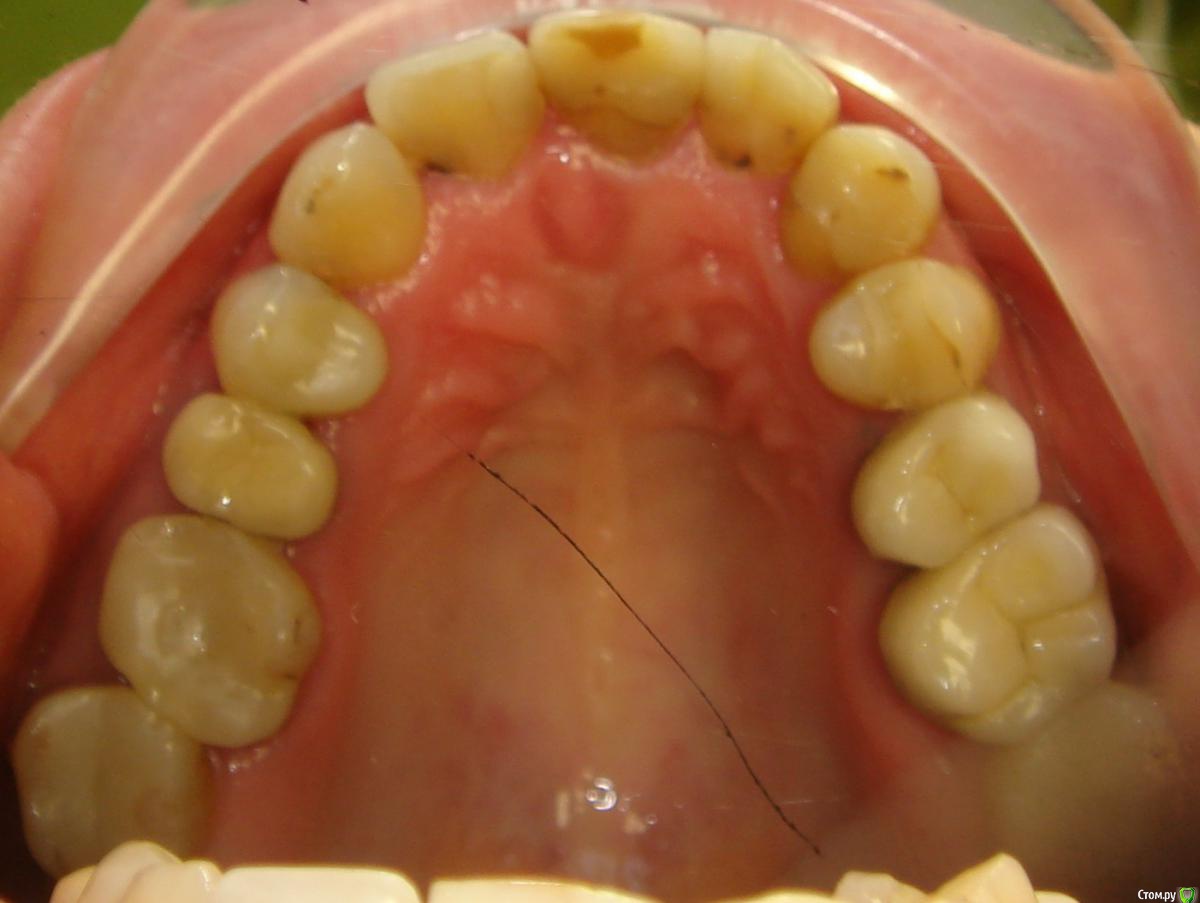

Здравствуйте, Коллеги! Хочу спросить совета по такому случаю. Пациентка 33 года. В детстве удалили 12 зуб, пространство закрыли на съемном аппарате. В подростковом возрасте удалили все остальные отсутствующие зубы. Сейчас носит бюгель. Вопрос такой: заниматься ли мне, как ортодонту формированием полноценного межчелюстного соотношения, или просто решить локальные проблемы и отдать на функциональную реабилитацию ортопеду? И если все-таки заниматься мне, то как??? Лечение такого третьего класса - элементарно для многопетлевой при наличии адекватной опоры, но вот такая адентия заставляет меня сомневаться. Заранее спасибо за ответы!